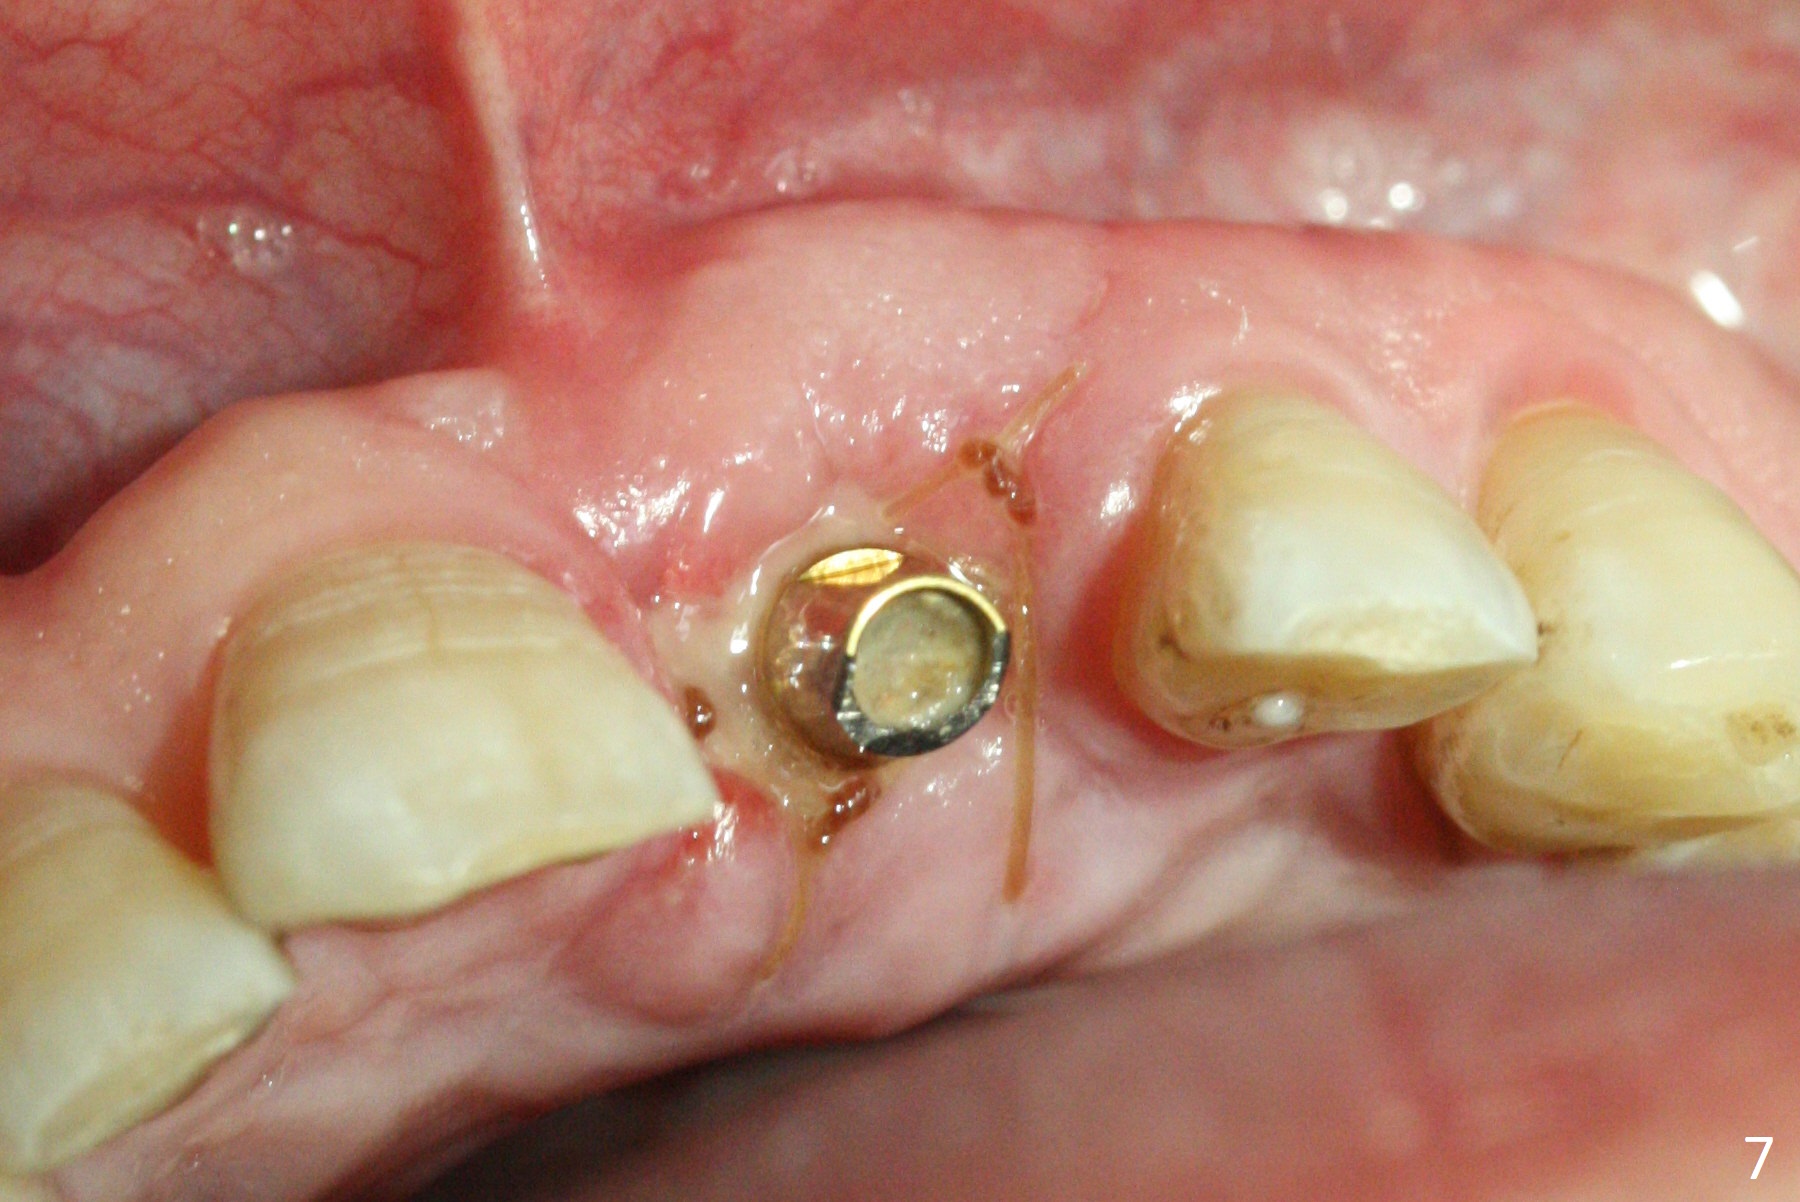

Preop examination shows mobility I of the teeth #8 and 10 and apparent occlusal trauma from #22-26 implant bridge. After occlusal equilibrium, incision reveals low, but moderate ridge at #9 (Fig.1). Fig.2a is a cross section of a normal upper incisor socket with thin buccal plate (B) and thick palatal one (P). It is difficult to initiate osteotomy in the oblique palatal wall when the buccal plate is resorbed (Fig.2b). In this case with horizontal buccal and palatal plate bone loss, the socket bottom is flat (Fig.2c), easy for osteotomy (Fig.2d green arrow, Fig.3). The initial osteotomy deviates mesial (Fig.3). To avoid perforation into the Incisive Canal, the trajectory is changed (Fig.4). After use of the final drill (3 mm), the coronal Incisive Canal is perforated. Following placement of a 3.5x13 mm implant and 4.5x5.5(4) mm abutment, Vanilla Graft is placed (Fig.5 *) to repair the perforation. Retrospectively, the coronal end of the Incisive Canal is revealed at incision (Fig.1 *). The initial osteotomy should be slightly more distal (Fig.3 black line). The buccal plate looks bulky due to placement of the abutment and bone graft 1 week postop (Fig.6,7 (crown dislodgement)). The bone graft appears to remain in place 2 months postop (Fig.8). Impression is taken because of instability of the immediate provisional (Fig.9 after Laser gingivectomy). The gingiva and buccal plate remain healthy 4.5 months postop (Fig.10). A permanent crown is cemented (Fig.11).